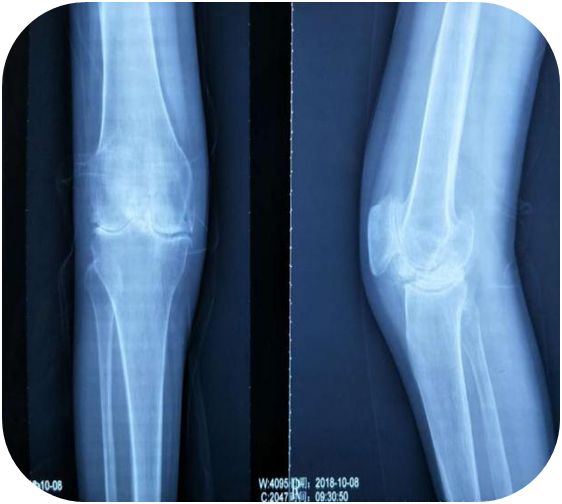

患者在住院期间,风湿病科主管医师普勇斌一直精心诊治、丁珊医师行针灸治疗,同时护士予中药封包、中药热奄包等治疗,但患者症状缓解不明显,查看患者右膝关节正侧位片发现:患者右膝关节骨质破坏严重,关节间隙明显变窄模糊,追问患者,患者诉3年前右膝就伸不直了,多家医院都考虑关节畸形严重,建议患者行膝关节人工关节置换,但患者出于经济情况等多方面考量坚持保守治疗,后由丁珊医师详细讲解了针刀治疗的风险及术后注意事项,患者签署了操作同意书,予患者行右膝小针刀松解术。

患者出院后也一直门诊坚持治疗,每月2次,期间行关节腔注射玻璃酸钠2次润滑关节,至2019年5月予患者复查右膝关节X片,患者膝关节间隙较前明显清晰,患者膝关节疼痛明显减轻,基本无疼痛,行走时感少许酸软无力,膝关节活动度较前明显增大,从原先腘窝下距离床面三拳明显减少到一拳,后患者陆续又行双肩、双肘关节小针刀松解术,疼痛也得到明显改善。

患者治疗前后膝关节X线片对比